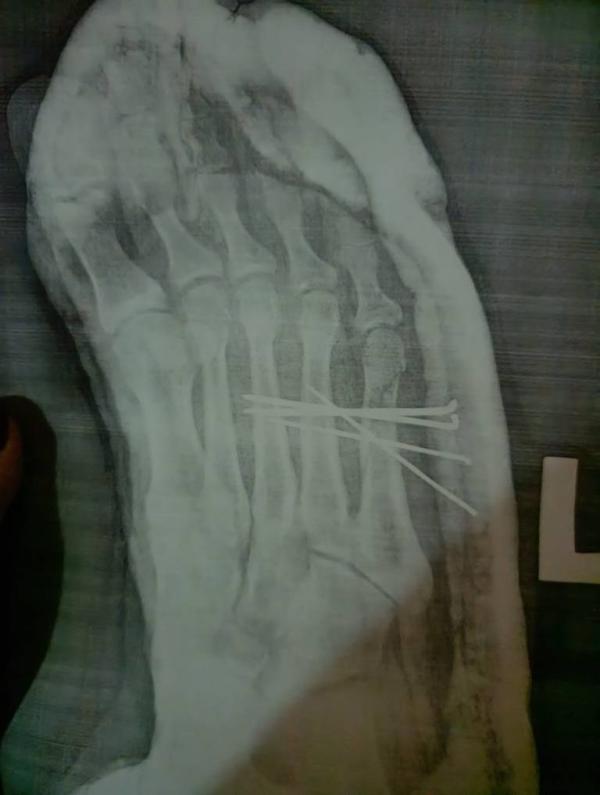

Девочки, может есть у кого-нибудь опыт ношения обуви Барука? Расскажите, как это, удобно, был ли дискомфорт? В ближайшее 6 недель предстоит носить, но мне так страшно почему-то. А на фото, причина ношения этой обуви 😔